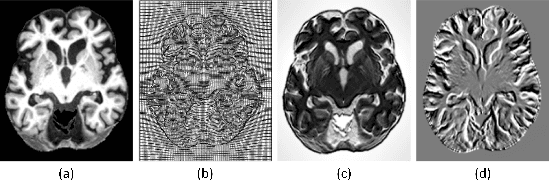

Abstract:Accurate segmentation of brain tissue in magnetic resonance images (MRI) is a diffcult task due to different types of brain abnormalities. Using information and features from multimodal MRI including T1, T1-weighted inversion recovery (T1-IR) and T2-FLAIR and differential geometric features including the Jacobian determinant(JD) and the curl vector(CV) derived from T1 modality can result in a more accurate analysis of brain images. In this paper, we use the differential geometric information including JD and CV as image characteristics to measure the differences between different MRI images, which represent local size changes and local rotations of the brain image, and we can use them as one CNN channel with other three modalities (T1-weighted, T1-IR and T2-FLAIR) to get more accurate results of brain segmentation. We test this method on two datasets including IBSR dataset and MRBrainS datasets based on the deep voxelwise residual network, namely VoxResNet, and obtain excellent improvement over single modality or three modalities and increases average DSC(Cerebrospinal Fluid (CSF), Gray Matter (GM) and White Matter (WM)) by about 1.5% on the well-known MRBrainS18 dataset and about 2.5% on the IBSR dataset. Moreover, we discuss that one modality combined with its JD or CV information can replace the segmentation effect of three modalities, which can provide medical conveniences for doctor to diagnose because only to extract T1-modality MRI image of patients. Finally, we also compare the segmentation performance of our method in two networks, VoxResNet and U-Net network. The results show VoxResNet has a better performance than U-Net network with our method in brain MRI segmentation. We believe the proposed method can advance the performance in brain segmentation and clinical diagnosis.